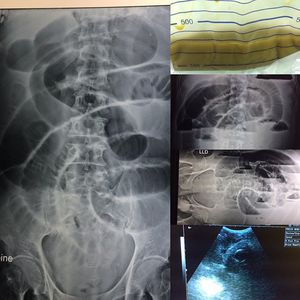

Bowel obstruction

Obstruction